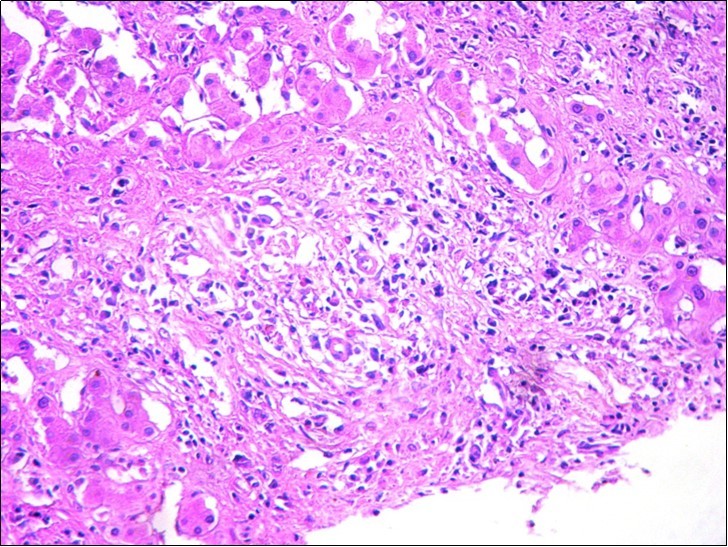

After a multidisciplinary concertation, the hepatectomy was recused because of the size of lesion, the uncertain nature of the lesion and the small remaining liver in case of surgery. The pathological examination was performed again showing inflammatory pseudotumor of the liver (Figure 3). The Polymerase Chain Reaction (PCR) of the specimen was positive. PCR BK made on liver biopsies molecular profile compatible with a hepatic tuberculosis despite the absence of a granulomatous reaction to histology

Figure 3.Hepatic biopsy showing a marked inflammatory reaction with a polymorphic infiltrate (HEx200)